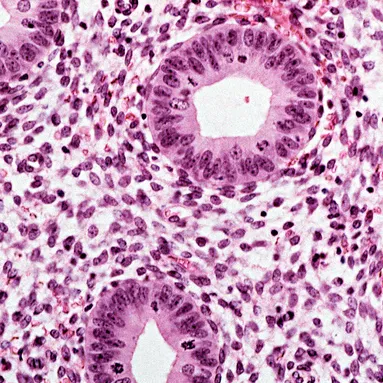

子宫由三层组成,外层薄壁称为子宫外模或浆膜,中间由环形肌、斜行肌和纵行肌组成肌层,最内层为子宫内膜。

内膜又分为两部分,内侧的功能层有许多腺体和结缔组织构成。

外侧为基底层,在每个月经周期子宫内膜脱落后由基底层再生形成功能层。

功能层的生长由卵巢分泌的激素调控。